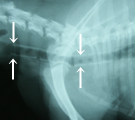

初診時胸部X線および気管支鏡所見。頚部気管尾側部から胸部気管の扁平化(矢印部分)。 第8病日胸部X線所見。シリコンステント(外径11 mm×長さ90mm)を留置した。 第147病日。気道ステントをEasy WallstentTM(外径12mm×長さ10mm)に交換した。 第259病日気管支鏡所見。右斜め下方部を残しステント内面の全域で上皮化が確認された。

経過:初診時身体検査所見にて、体温38.3(℃)、心拍数104(/min)、呼吸数60(/min)。持続性ストライダーを伴った急性呼吸困難、吐出およびRetchingがみられた。気管虚脱および食道内異物と暫定診断した。胸部X線および透視所見にて、頚部気管尾側部から胸部気管の扁平化(図)、食道造影で食道運動性低下が確認された。全身麻酔下で上部消化器内視鏡検査を行ったが食道および胃内異物はみられず、気管支鏡検査では第5頚椎前端から第7頚椎尾端レベルの気管で完全虚脱がみられた(図)。主気管支以降に虚脱はなかった。よって、気管虚脱GradeIVと診断した。緊急に完全虚脱部位にシリコンステント(外径9mm×長さ55mm)を可及的に留置し覚醒させたが、2時間後にステントは喀出され喘鳴が再開した。ステロイドと抗生剤を吸入療法と注射にて7日間投与を続け初期症状を安定化させた。第8病日、外径11mm×長さ90mmのシリコンステントを留置した(図)。4日後より咳は減少し活動性が増加した。第15病日に血液ガスで換気能と酸素化は正常を示し(それぞれPaco2 37 mmHg、Pao2 80 mmHg)退院とした。しかし次第に咳症状が悪化し、第112病日にはPao2 72 mmHgおよびA-aDo2 39 mmHgと肺機能低下を示し、気管支肺胞洗浄液(BALF)の解析では総細胞数3665/mm3と著増し好中球が71%と多数を占めた。有意な起炎菌は検出されず、排痰障害が示唆された。排痰障害改善のため第147病日シリコンステントを抜去し、外径12mm×長さ10mm[full open]の円筒型メッシュ状の自力拡張型金属ステントEasy WallstentTMを留置し気管の十分な拡張を得た(図)。翌日より咳は著明に減少し、4日後に全身状態が回復した。6日後には肺機能正常化し(Pao2 82 mmHgおよびA-aDo2 21 mmHg)退院となった。第259病日、血液ガスにてPao2 81 mmHg、A-aDo2 26 mmHgおよび気管支鏡検査にてBALF総細胞数255/m3を示し、再留置前の排痰障害による肺機能低下は改善されていた。また、ステント内面のほぼ全域にわたる上皮化も確認された(図)。全経過を通じて自宅で、排痰補助、気道内炎症抑制および肉芽形成防止のため、生食3 ml、ゲンタマイシンあるいはアミカシン 0.1 ml、およびデキサメタゾン0.1 mlを混じた薬液の吸入療法を1日2回行った。197病日より発咳予防ためブトルファノール0.05mg/kg q12h POを始めた。激しい運動は避け、なるべく吠えないように管理した。